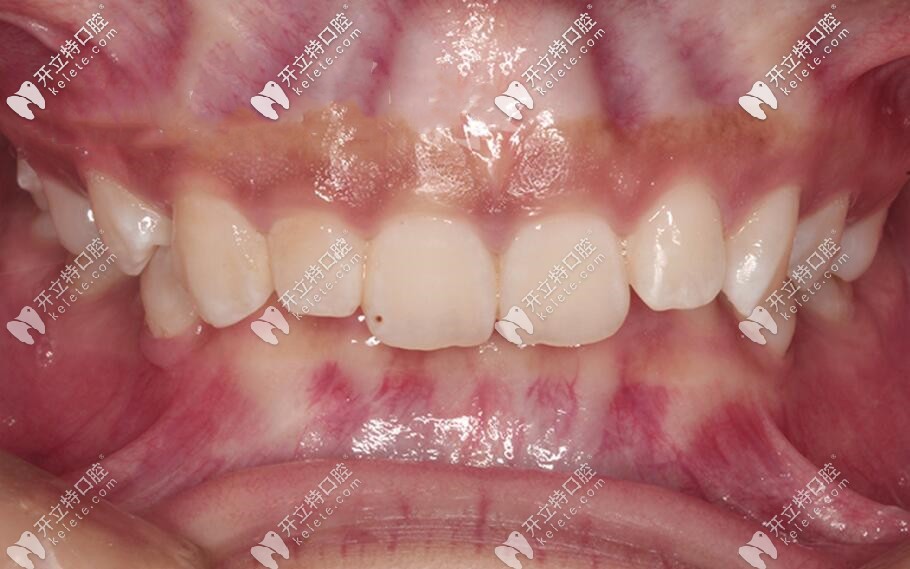

妥妥的三度深覆合↓↓↓

內(nèi)傾型三度深覆合矯正后效果圖▼